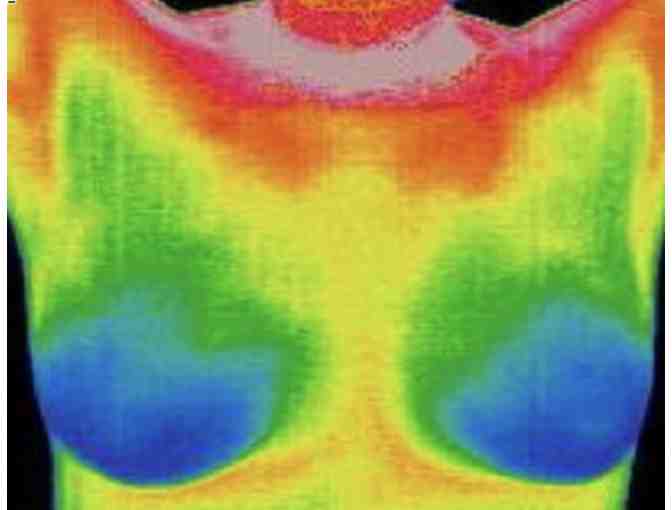

Establish a Breast Health baseline with a sensitive and completely safe scan, provided by the Thermography Center of Sonoma County.